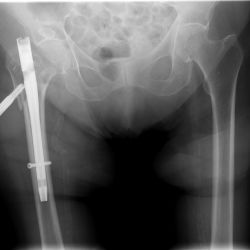

Schlecht festgeschraubt